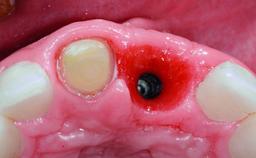

Replacement of an Upper Right Central Incisor with Root Resorption: Ridge Preservation, Delayed Placement of an NC Bone Level Roxolid Implant

Bone Augmentation Horizontal|Simultaneous|Staged

Augmentation Materials Autogenous chips|Xenogenous|Membrane

Bone Volume Deficient horizontally, requiring prior grafting